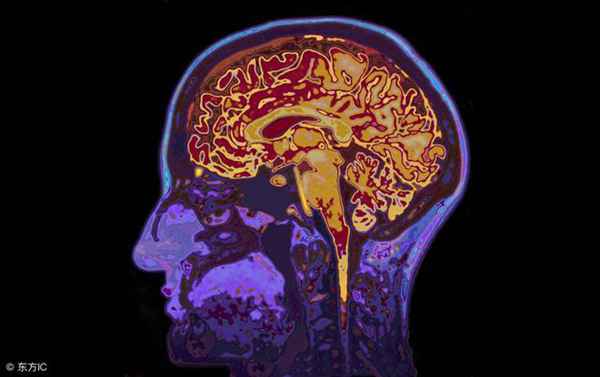

做核磁共振的时候,机器会提供一个大的磁场,通过检测氢原子在磁场下的运动,来获得影像学图像。核磁功能也是有辐射的,属于电磁辐射,我们常用的手机、电视和电脑,都有电磁辐射。电磁辐射对人体是无害的,孕妇也是可以做核磁共振检查的。所以,核磁没有“辐射”,指的是核磁没有电离辐射,是相对安全的,这种说法是对的。但是,要纠正一个错误的观念,CT的伤害并不是大家想象的那么大,CT确实有一定的辐射,但远远达不到致癌的危险。你坐飞机还有辐射呢?坐几次飞机就等于做一次CT的辐射量。每年做一到两次CT是没有问题的,而且,现在还有低剂量的CT检查,辐射剂量更小。而且,尽管核磁共振确实没有电离辐射,但是MRI检查也是有缺陷的,并不是所有的组织和器官都适合MRI检查。 MRI有以下缺陷: